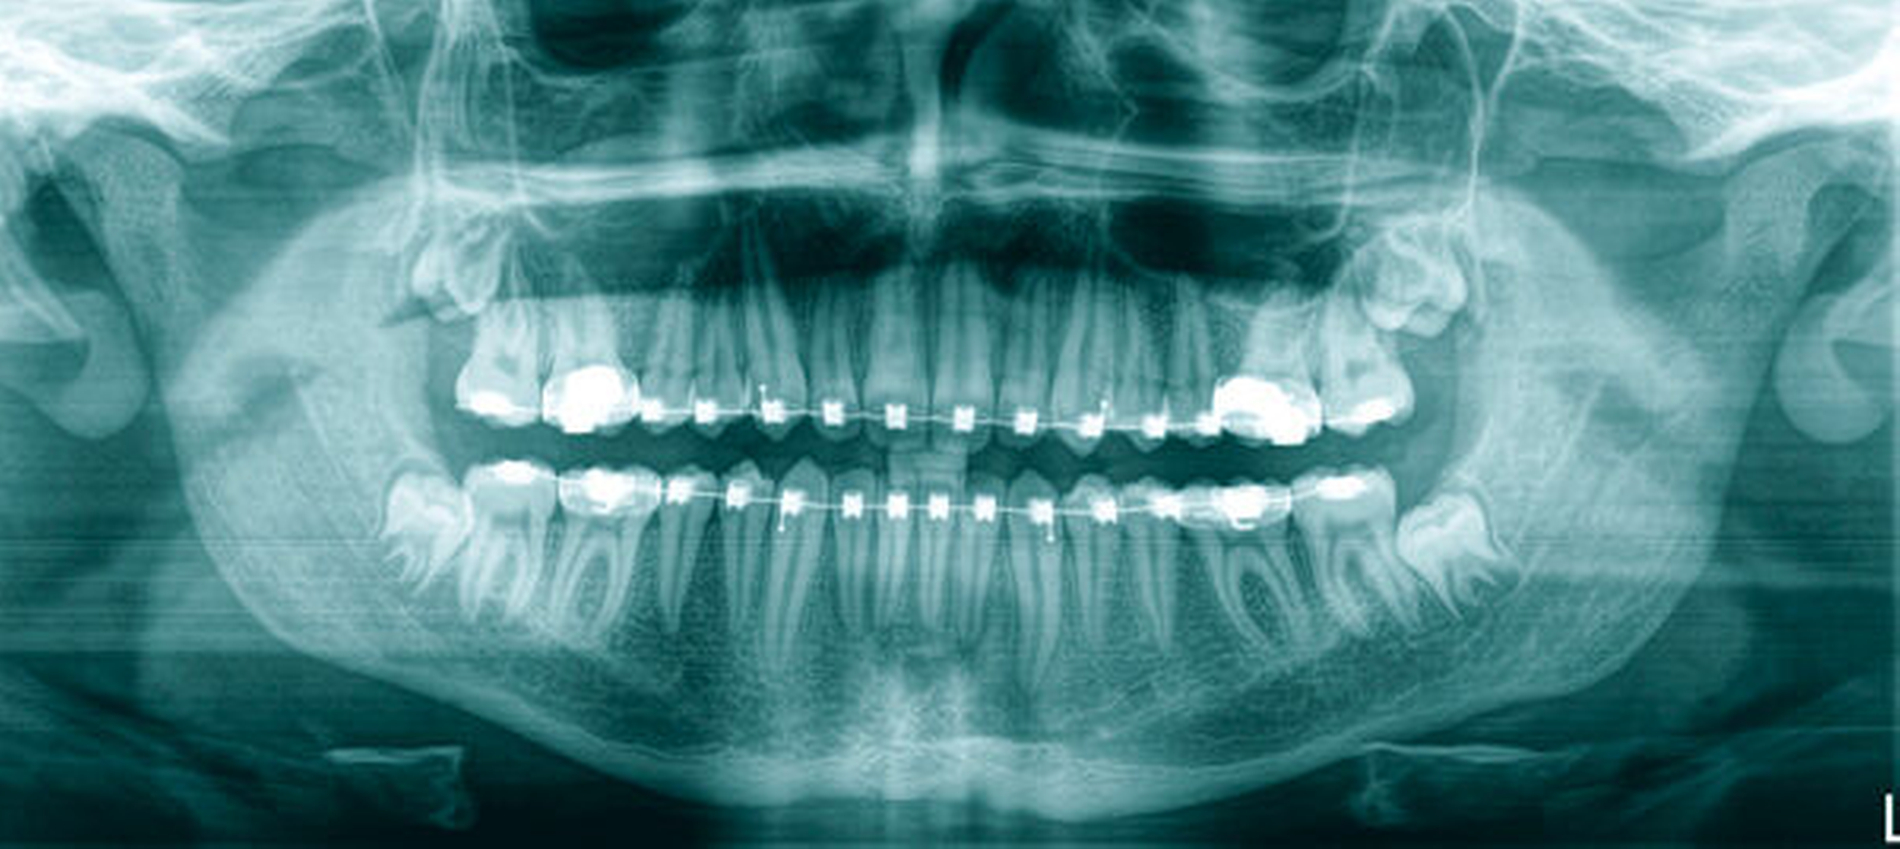

Das angefertigte OPT (Abbildung 1) zeigte einen ektopen, überzähligen Zahn 13a. Nach Komplettierung der Bildgebung durch eine Computertomografie (Abbildungen 2a und 2b) fand sich der Zahn kranial im rechten Nasenboden gelegen. Nebenbefundlich konnte eine polypöse Schleimhautschwellung der rechten Kieferhöhle festgestellt werden.

Acht Monate postoperativ lag bei der klinischen sowie radiologischen Kontrolle ein unauffälliger Befund vor. Das Verlaufs-OPT zeigte einen zeitgerechten Befund im rechten Oberkiefer nach Zahnentfernung und Kieferhöhlenrevision (Abbildung 4). Der Patient ist postoperativ nach wie vor beschwerdefrei. Weitere röntgenologische Verlaufsuntersuchungen sind nicht geplant.